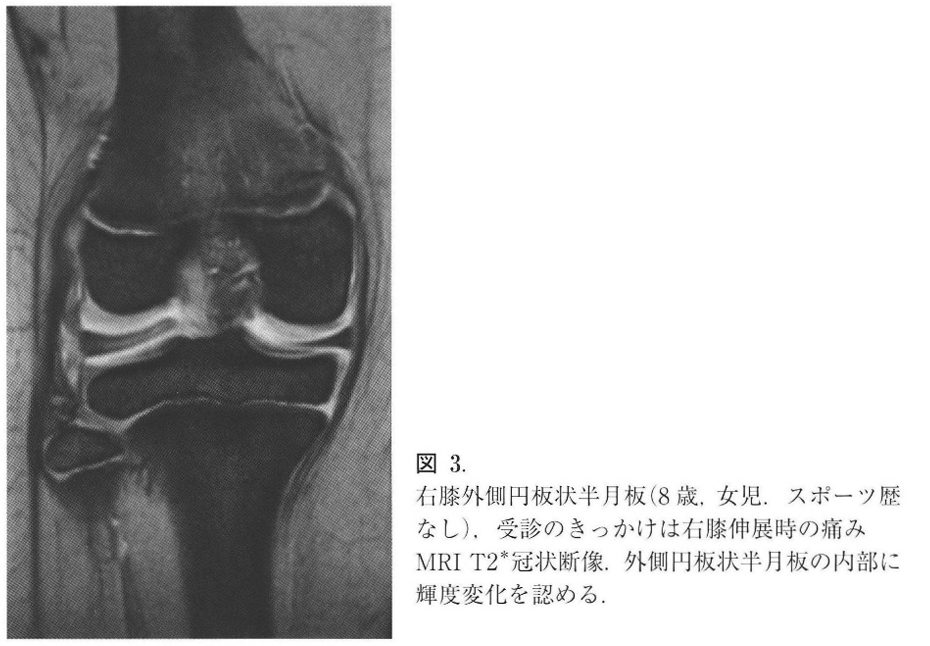

半月板とは膝の骨と骨の間のクッションの役割をする構造物ですが、胎児の頃はまん丸の形をしていて発生とともに徐々に三日月の形になっていきます。円板状半月とはイメージで言うと半月板がまん丸のまま残っているような状況です。ですので、骨と骨の間に挟まれて損傷し膝の痛みになりやすい方が一定数いらっしゃいます。

また円板状半月板は外側半月板がほとんどで,正常の半月板よりも厚く,内部の線維配列も異常で損傷を受けやすく,損傷すると伸展障害,膝の外側の痛み、ひっかかりなどが生じます。

診察とレントゲン、MRIで診断します。診察では痛みの場所、膝をひねったときに痛くないかなどをチェックし、レントゲンでは骨の異常がないかを確認します。最終的にMRIを撮影し、確定診断となります。